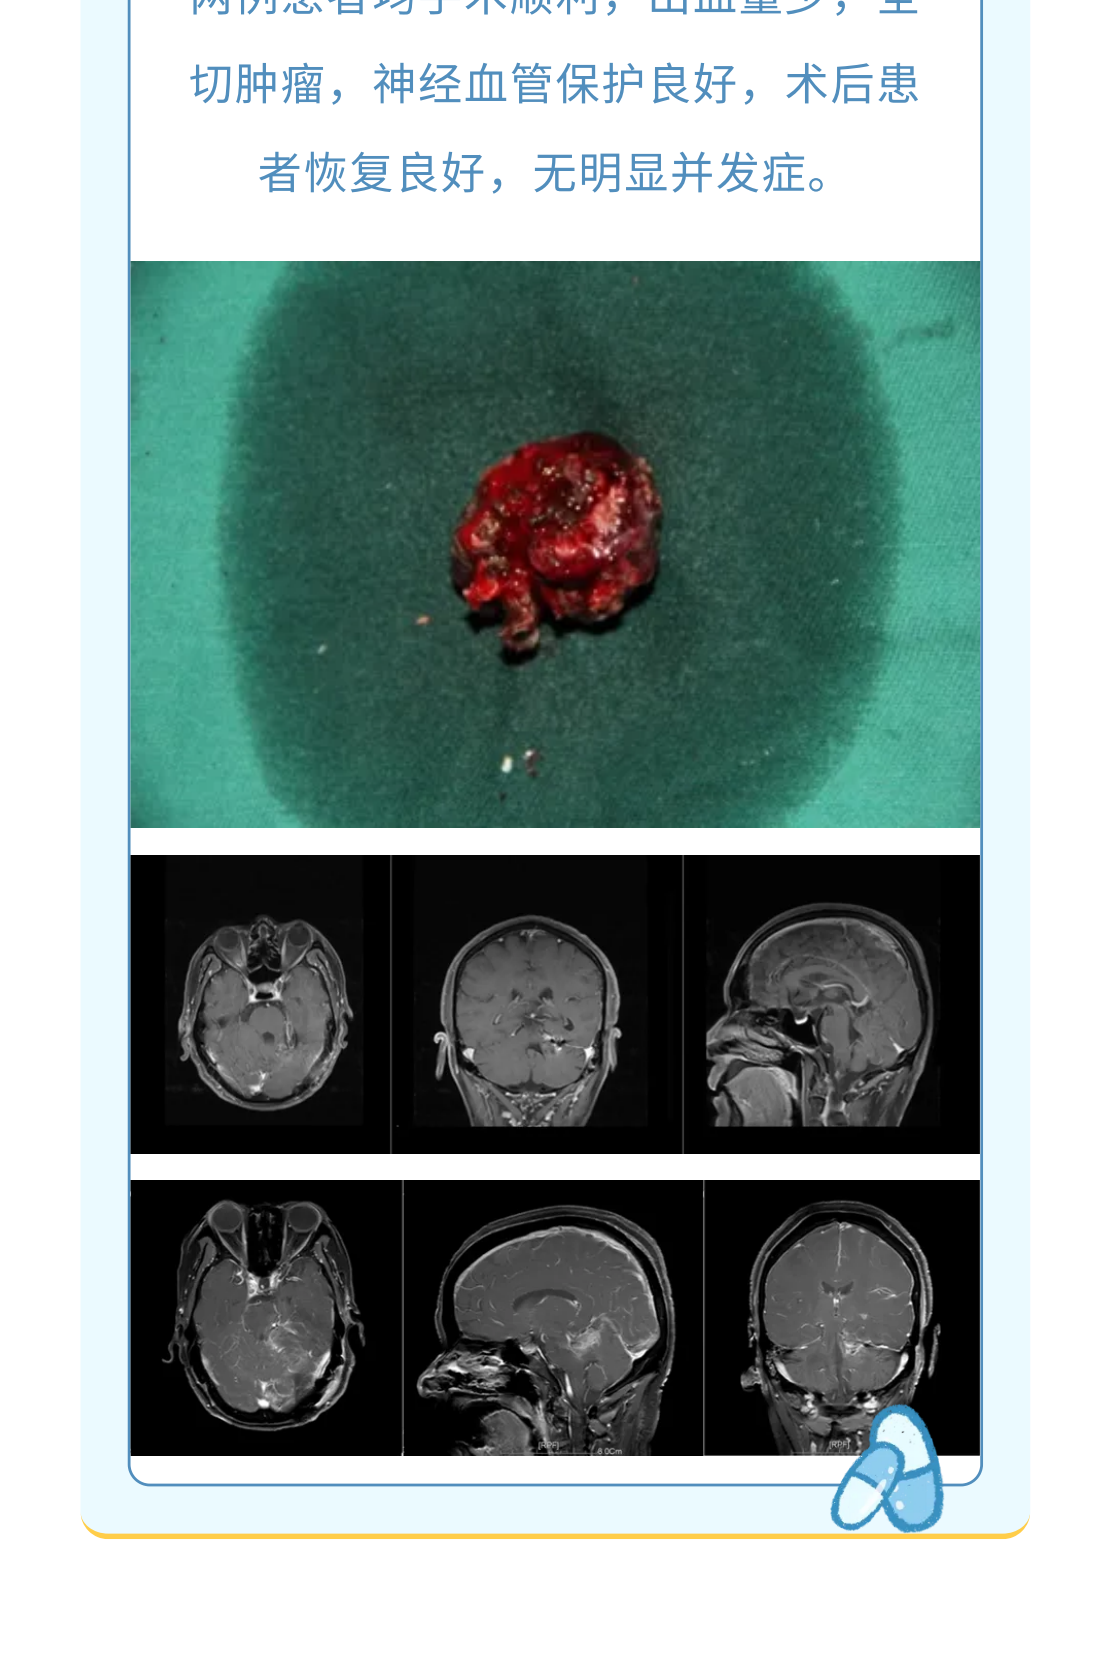

神经导航辅助下改良枕下天幕上入路治疗复杂小脑山坡实质性血管母细胞瘤

血管母细胞瘤( 血管网状细胞瘤、血管网织细胞瘤):为良性肿瘤, 有人认为其起源于血管周围的间叶细胞, 好发小脑中线旁,占颅内肿瘤的1%,后颅窝肿瘤的7%; 主要发生于成人(30~40岁多见);儿童期和老年人少见,男性较女性多见; 分为散发性和家族遗传性两种,后者表现为VHL病。多发者高度提示VHL病。